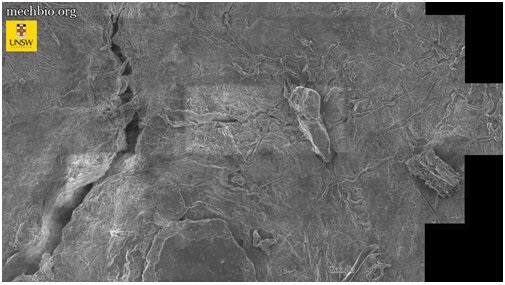

برای درک بهتر ترافیک سلولی در بدن انسان، تصاویر متعددی از استخوان لگن خاصره با استفاده از میکروسکوپ الکترونی روبشی تهیه شد؛ سپس این حجم عظیم از دادهها با استفاده از الگوریتمهای گوگل برای بزرگنمایی و کوچکنمایی بر روی بافت استفاده شد.

«نوت» تأکید کرد: برای نخستینبار، توانایی مشاهده چگونگی دریافت مواد مغذی توسط سلولهای منفرد و ارتباط آنها با یکدیگر را پیدا کردیم. این روش میتواند مسیر را برای توسعه روشهای درمانی ناشناخته و اقدامات پیشگیرانه آرتروز مفصل ران هموار کند.

در حال حاضر از این فناوری برای مشاهده بافت لگن و درک بهتر آرتروز و دردهای مفصلی مزمن در افراد سالمند استفاده میشود، اما محققان امیدوارند از این فناوری در آینده نزدیک برای بررسی سایر بافتها نیز استفاده کنند.